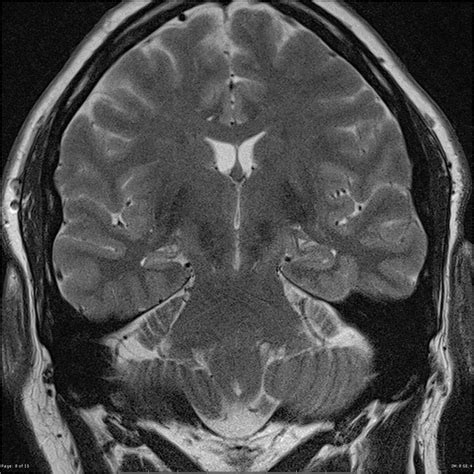

MRI (Magnetic Resonance Imaging) The "Gold Standard" to visualize hippocampal atrophy, volume loss, and increased signal intensity.

⚠️ Note: High-resolution MRI protocols, specifically designed for epilepsy (often called an epilepsy protocol MRI), are essential for detecting subtle signs of MTS that might be missed on standard clinical scans.